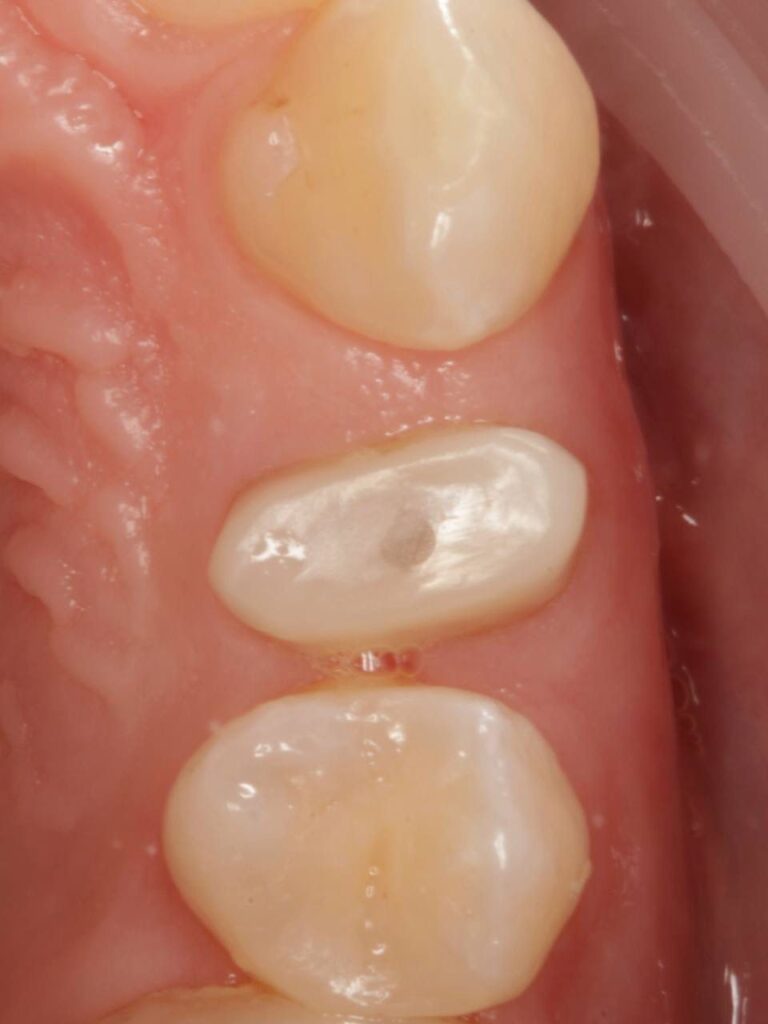

Специализация: терапия(эндодонтия), ортопедия, имплантология.